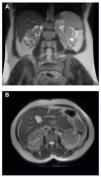

Figure 3. MRI of case 3 where the kidneys retain their shape, with multiple small cysts (TRV=603ml). A) Coronal view B) Axial view